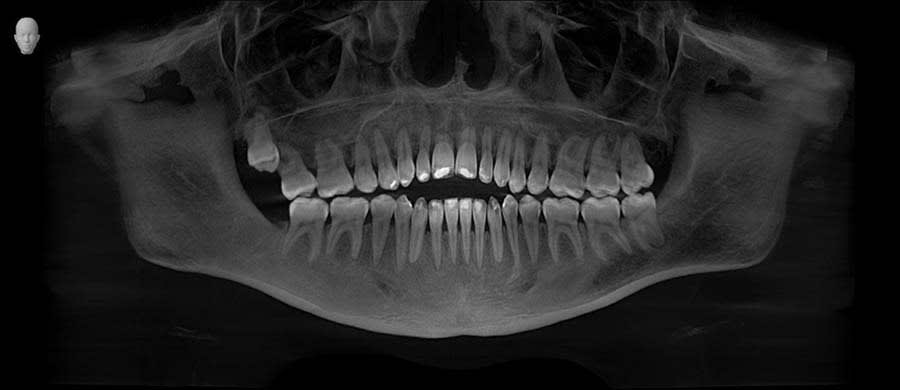

A 26-year-old female patient presented with complaints of unsatisfactory smile esthetics, difficulty biting food, and speech issues. Her medical history was unremarkable. Clinical examination revealed an anterior open bite, mild chronic generalized periodontitis, and impacted third molars in the third and fourth quadrants. Accurate diagnosis of occlusal issues was critical in the treatment planning.5

A panoramic radiograph was recorded (Figure 1), followed by a clinical examination (Figure 2). A jig was fabricated to stabilize centric relation (CR) (Figure 3), and jaw movements were analyzed using a virtual articulator in CAD software (exocad, exocad.com) (Figure 4). Digital wax-ups and guides were employed to enhance surgical and restorative accuracy.6